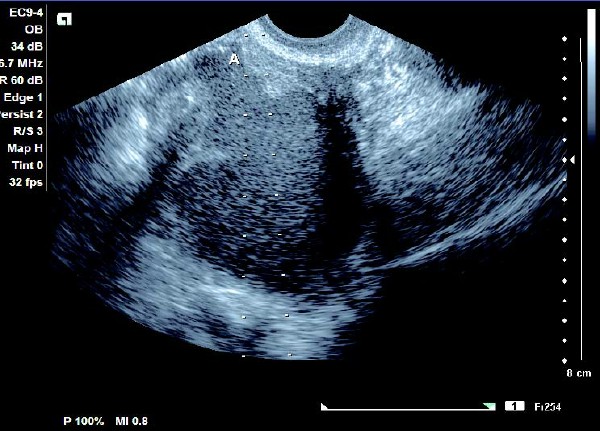

(1)单侧或双侧卵巢内呈现椭圆形或圆形无回声暗区,其内充满弱回声光点,囊肿直径一般为5~6 cm,大于10 cm 的较少见。

(2)壁较厚,囊内充满细小均匀点状回声,后方回声增强。

(3)常与周围组织有粘连,边界清晰。

患者,女,35岁。每次月经量少,痛经,近来行经期延长、疼痛加重来院诊治。超声报告显示子宫前倾位,子宫体大小为:5.9cm×5.1cm×4.8cm,形态规则,边界清晰,宫避回声匀称,宫腔线居中,内膜厚度0.6cm,宫内未见异常回声。右侧卵巢内可见大小约5.2 cm×4.9cm的无回声区暗区,壁厚,内壁欠光滑,内见密集细光点,边界清晰。CDFI探测囊壁及囊腔内无血流信号。

超声提示:右侧卵巢巧克力囊肿